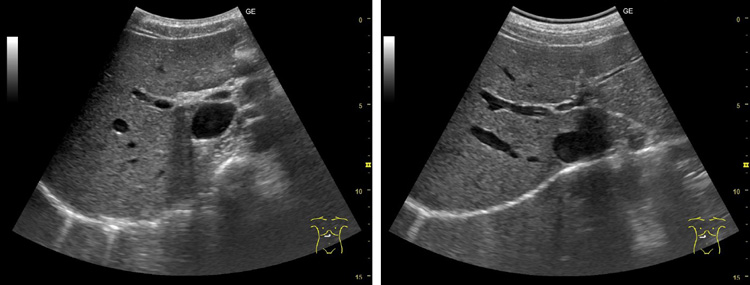

研究團隊製作了規格為5mm厚、5cm見方的研發用凝膠墊,並以4名健康人為研究對象開展了實驗。實驗中分別使用凸陣探頭對肝臟、膽囊等腹部臟器進行檢查,使用線陣探頭檢查位於體內較淺部位的頸動脈是否形成斑塊,使用扇掃探頭觀察心臟內部瓣膜的活動情況。結果顯示,新款固態凝膠墊拍出的影像在清晰度和診斷精度上,與液體凝膠並無明顯差異。研究團隊還採用1~5分的5級評分製(分數越高代表滿意度越高)對受檢者的檢查滿意度進行調查,結果顯示,既往液體凝膠的評分基本停留在1~2分,而新開發的固態凝膠墊的評分達到了4~5分。

使用液體凝膠進行腹部超音波檢查得到的肝臟影像(左)與使用新開發的固態超音波診斷用凝膠墊得到的影像(供圖:近畿大學醫學部植原拓也講師)